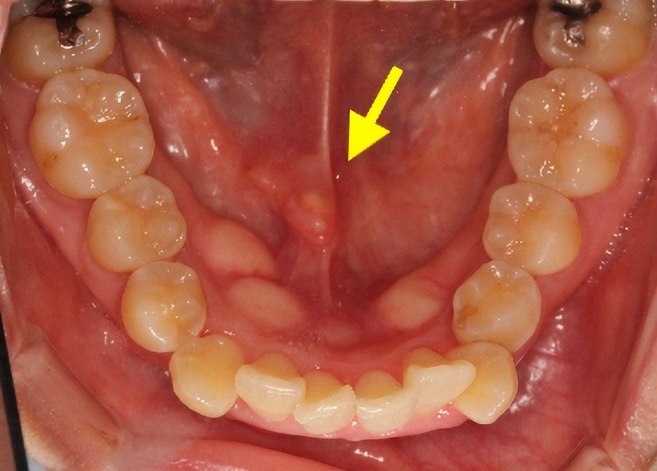

唾液腺結石並非一種罕見疾病,它主要發生在三大唾液腺:頷下腺、舌下腺和腮腺。以我的經驗,頷下腺是最常受影響的部位,約占所有病例的80%,這是因為它的導管較長且彎曲,容易積聚沉積物。記得去年我治療過一位中年患者,他的唾液腺結石大小僅有米粒般,卻在進食時引發劇痛,這提醒了我:即使結石微小,也能造成嚴重不適。唾液腺結石的形成過程類似腎結石,但影響更集中在口腔區域,我總是強調早期診斷的重要性,避免它演變成慢性問題。

發生位置與臨床影響

唾液腺結石的位置直接決定了症狀嚴重程度。舉例來說,腮腺結石較少見,但一旦發生,可能導致臉部腫脹更明顯。我曾遇過一名年輕女性,她的舌下腺結石引發了反覆感染,這讓我深刻體會到:位置差異會改變治療策略。總而言之,唾液腺結石若未及時處理,可能引起腺體功能退化或慢性發炎,進而影響咀嚼和說話能力。

常見的唾液腺結石手術包括內視鏡取石術和開放式手術。前者是我的首推方法——透過細小導管插入內視鏡,直接夾出結石,創傷小且恢復快。記得一位患者因大型頷下腺結石導致反覆感染,我們用內視鏡在30分鐘內解決,術後當天就能回家。另一種是唾液腺切除術,適用於嚴重損傷的腺體,但這是最後手段。唾液腺結石手術的成功率取決於結石位置,我總在手術前用CT掃描精確定位。